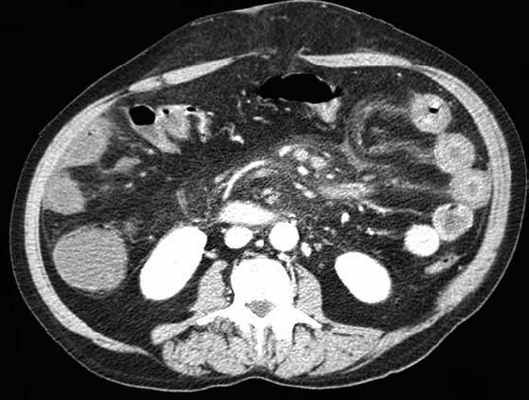

УЗД признаки тонкокишечной непроходимости

Основные УЗ-признаки при непроходмости- это визуализация расширенных петель тонкой кишки, сниженная перистальтика, свободная жидкость между петлями (танга) и в брюшной полости. Также УЗИ иногда позволяет обнаружить причину обструкции, например, опухоль, утолщение стенок терминального сегмента подвздошной кишки при болезни Крона и т.д. УЗИ может решить диагностическую дилемму при неоднозначных рентгенологических признаках на обзорной рентгенограмме брюшной полости. Лимит метода заключается в низкой специфичности при оценки состояния брыжейки, а также зависимость качества диагностики от конституции пациента и опыта оператора.

примеры сонограмм с расширенными петлями тонкой кишки

УЗИ позволяет прекрасно лоцировать свободную жидкость в брюшной полости